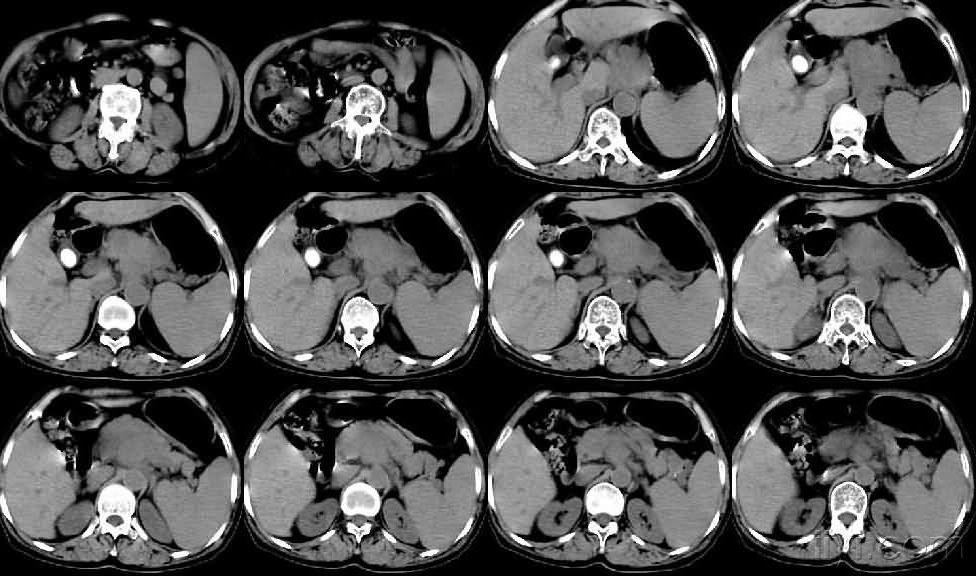

胰腺体尾部乏血供占位(对比钩突),包饶脾动脉(围管浸润),支持胰腺癌.

胰头占位患者,ct未见肿瘤,核磁提示胰腺癌,影像报道结果不一致,是手术

【病例讨论】胰腺钩突部肿瘤,性质?手术?手式? [病例帖]

胰腺增强ct影像显示肿瘤位于胰头钩突,(后续图片稍许血腥,请谨慎观看)